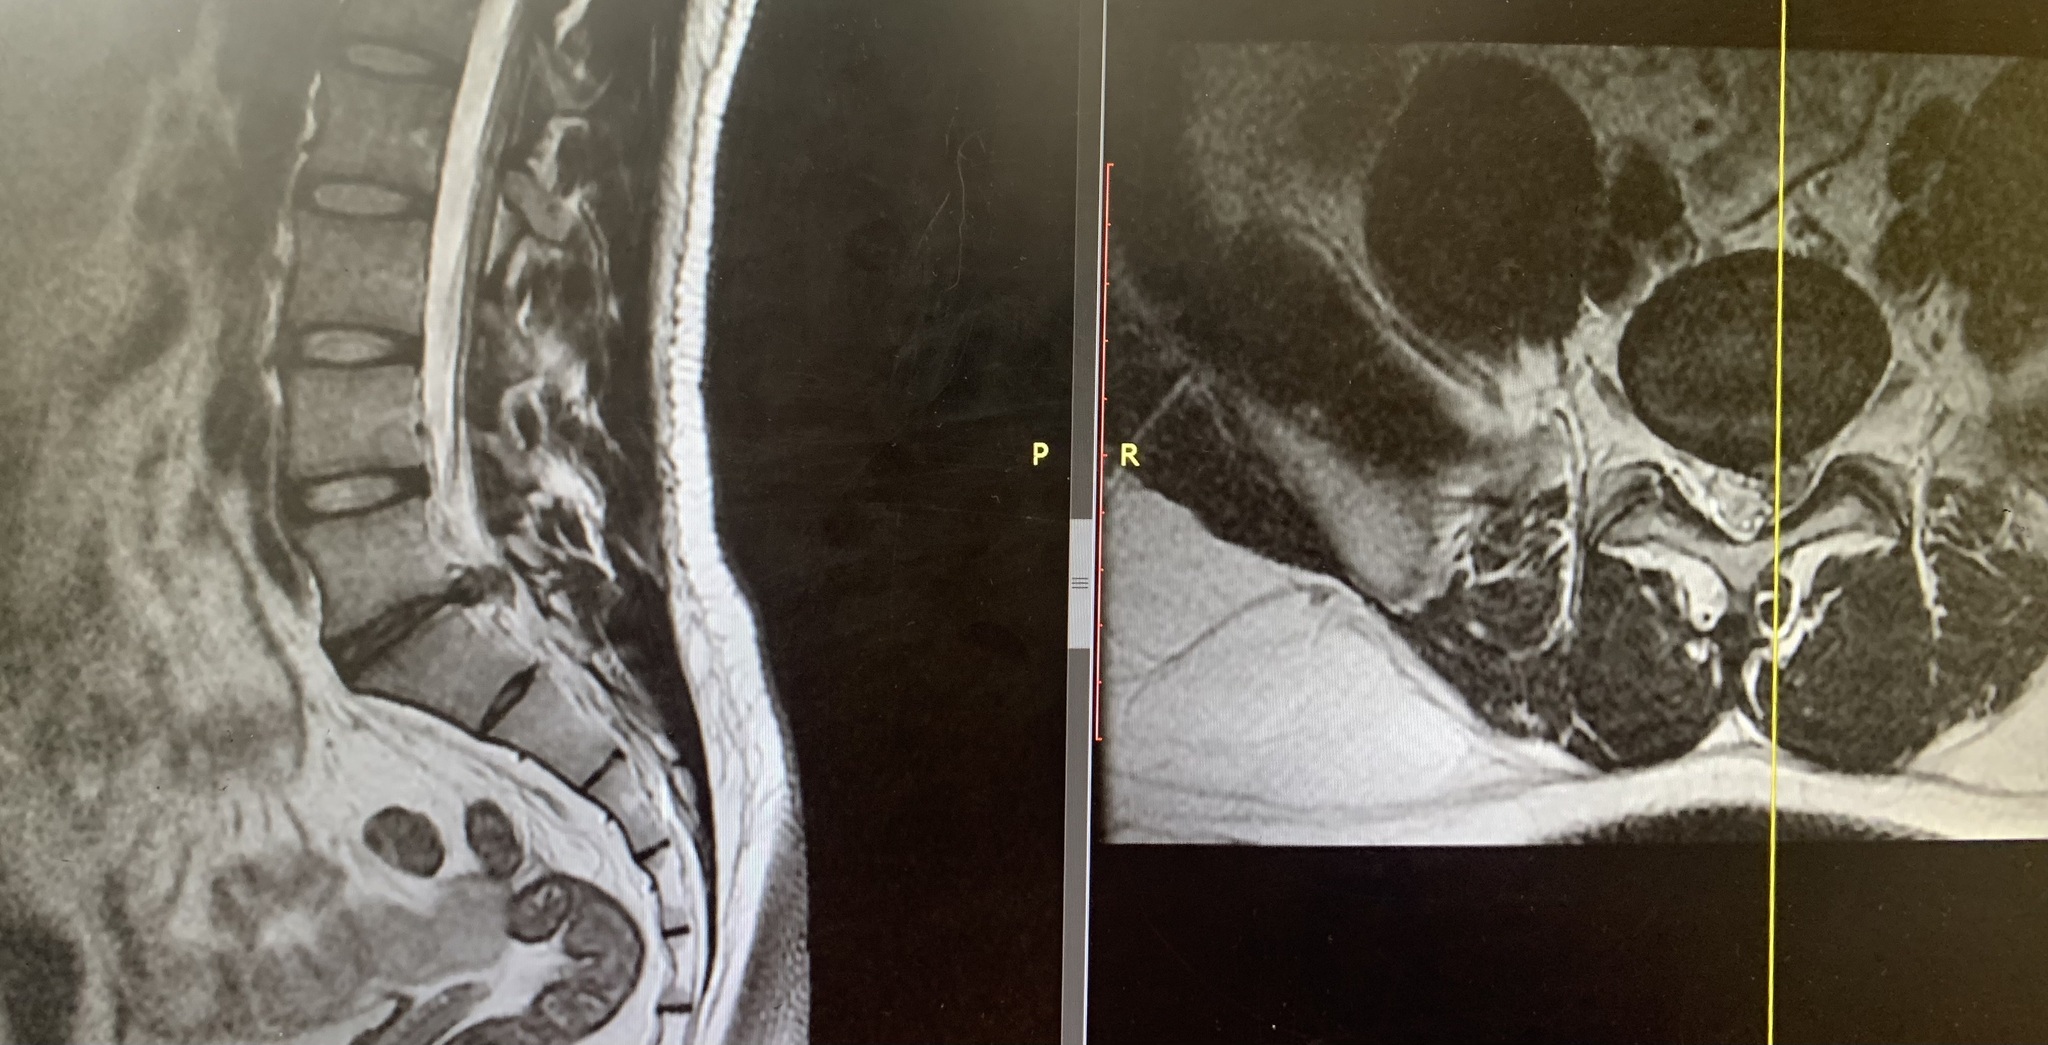

Нужно ли оперировать такую грыжу межпозвоночного диска? (11 мм)

Приходил пациент вот с такой грыжей диска, но оперировать мы его не стали)). Вопрос на обсуждение)))